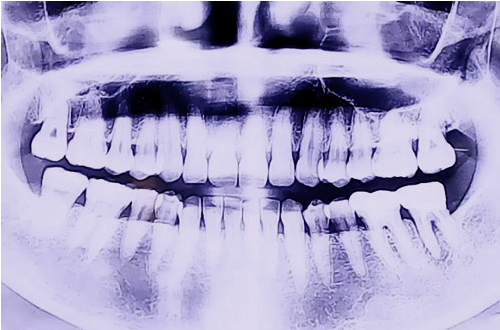

BEFORE

어금니 신경치료 및 보철치료 후 주위 잇몸에 심한 염증이 발생하여 내원하신 환자분입니다.

문제가 되는 어금니 2개를 발치 후, 잇몸의 염증이 나아질때까지 기다리며 관리를 도와드렸고, 염증이 모두 없어진 것을 확인한 후 뼈이식과 함께 임플란트 수술을 진행하였습니다.